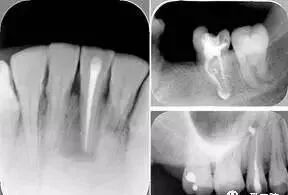

( 1 )直线通路:根管治疗时需要一个直线通路,直线通路能够达到根尖三分之一

测量标准:以允许根管器械直线并直接进入根尖 1/3 且不接触冠方各壁为标准。

( 2 )髓腔其他改变:如髓室顶、继发性牙本质、修复性或增龄性牙本质。见左图。

右图中有继发性牙本质,切削后获得直线通路